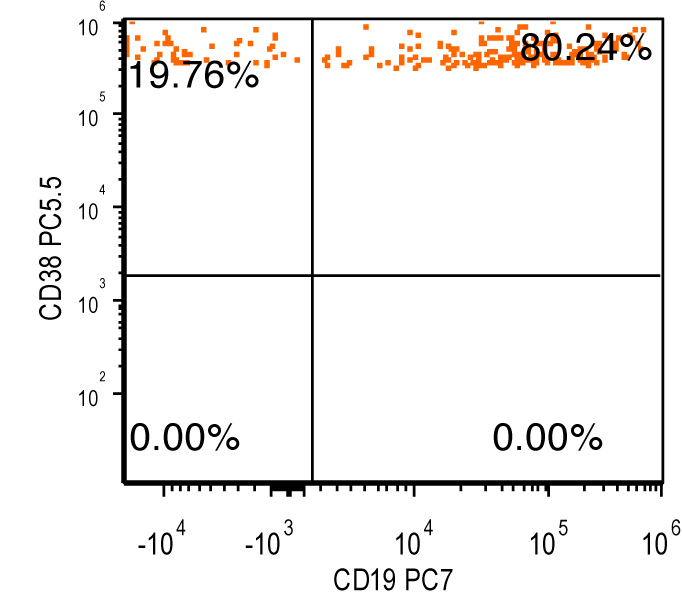

- Flow cytometry: monoclonal B cells with typical immunophenotype and monoclonal plasma cells

- Immunophenotype of LPL cells: IgM+, CD19+, CD20+, CD22+, CD25+, CD10-, CD23-, CD103-, variable CD138

- Immunophenotype

- Positive: IgM, CD19, CD20, CD22, CD79a, CD25 and CD38 frequent expression

- Negative: CD5, CD10, CD103, CD23; however, CD23 expression is not uncommon in some cases

Flow cytometry description

Flow cytometry images

Contributed by Ling Zhang, M.D. and Caroline An, M.D.